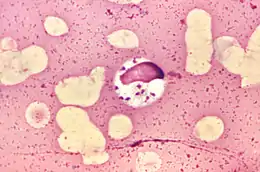

![]() Leishmania donovani у клітині кісткового мозку | ||||||||||||||||

Для розвитку лейшманій потрібні два хазяїни. Першим із них є москіт, в крові якої розвиваються і розмножуються лейшманії в джгутиковій промастиготній формі (розмір 10-15мкм)[7]. Другим хазяїном є представник хребетних, в тому числі і людина, в організмі якого збудник перебуває в амастиготній безджгутиковій формі (розміри суттєво менші від 2 до 5 мкм). Тут лейшманії знаходяться переважно в середині макрофагів (внутрішньоклітинно) — особливо в органах системи мононуклеарних фагоцитів (раніше — ретикуло-ендотеліальної системи).